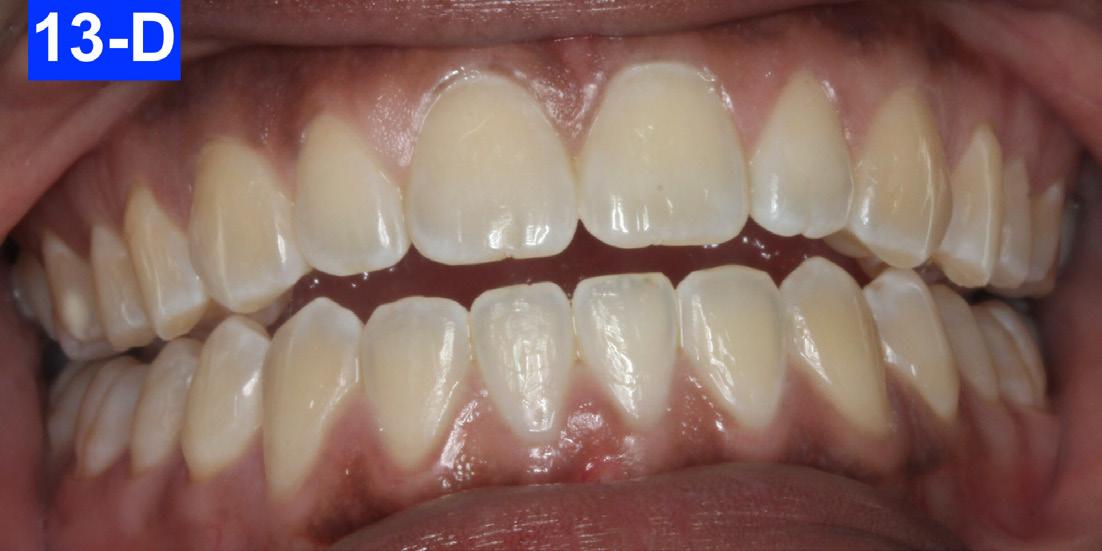

Figures 12-A to 12-M show the post-treatment images at the time of insertion of the retainers. We had an opportunity to evaluate the patient’s occlusion three years post-treatment. Compared to the initial post treatment evaluation, it was noted that the occlusion had settled into an even more stable position after three years.

The patient reported that she had not been wearing her retainer, no longer sucked her thumb, and no longer performed the OMT exercises (Figures 13A-O).

Fig. 13-D: 3 years post-treatment, teeth apart